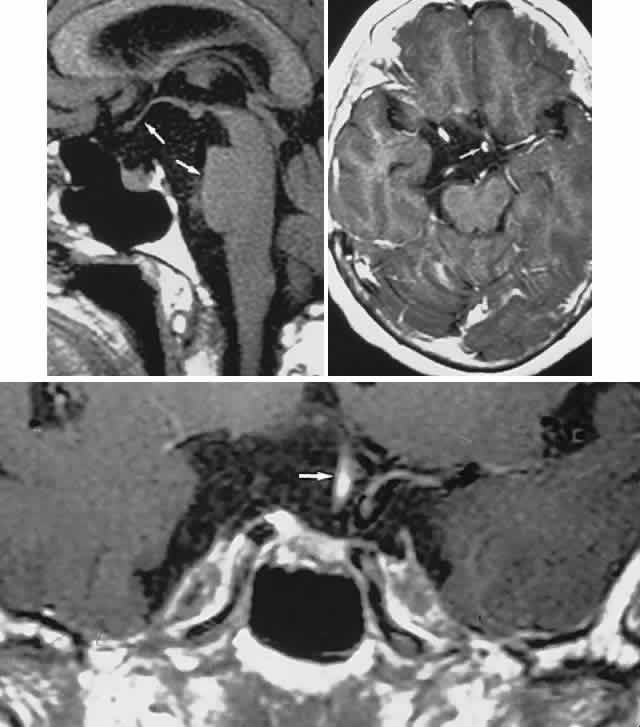

Fig. 3. Neuroimaging of pituitary adenomas. A. Axial computed tomography (CT) section shows a round tumor mass filling the suprasellar cistern; ring enhancement (arrows) indicates subcapsular hemorrhage. B. Contrast-enhanced coronal CT section through a large invasive adenoma. Note encasement of the carotid artery (arrows) and the position of the middle cerebral artery above (arrowheads). C. Axial CT section shows lateral expansion into the cavernous sinuses (white arrows) and a necrotic cyst (black arrow). D. Subfrontal superior extent of the mass. Note the middle cerebral arteries. E. Magnetic resonance imaging of a large lobulated prolactinoma, with suprasellar extension. Note the distortion of the third ventricle (open arrows) and extension toward the temporal lobe (long arrow); the tumor has not involved the sphenoidal sinus (s). F. Chiasm (arrowheads) is draped on the superior surface of the tumor (TR, 550 milliseconds; TE, 26 milliseconds). G. Sagittal section shows suprasellar growth with the chiasm above (arrowheads); the sella (arrows) and sphenoidal sinus (s) are normal (TR, 850 milliseconds; TE, 26 milliseconds). H. Hyperintense signal (TR, 2000 milliseconds; TE, 60 milliseconds) indicates the partial cystic character. Sagittal (I) and axial (J) sections with head tilt to the right, in case of a large cystic adenoma with an interface level between newer blood (white arrow) and older blood (black arrow) (TR, 800 milliseconds; TE, 30 milliseconds). K. Signal difference is intensified (TR, 2100 milliseconds; TE, 80 milliseconds). L. Hemorrhage (bright signal, arrow) in a pituitary adenoma with headache and bitemporal field depressions. M. Without interventions, 2-month follow-up showed spontaneous involution, with normal pituitary gland (arrow), stalk, and chiasm.

In addition to the radiologic implications mentioned previously, specific points should be emphasized. Contrast-enhanced CT and, especially, MRI have replaced all previous radiologic techniques in the detection and anatomic assessment of sellar and juxtasellar lesions. MRI has also the inherent advantage of using no radiation, nor does it require iodinated contrast injections. Although thin-section contrasted CT does indeed disclose most lesions, bone changes, and recent hemorrhage, MRI is superior in delineating distortions of optic nerves and chiasm, in displaying arteries, and in revealing fat, hemorrhage, or cyst (see Figs. 3E through M). Indeed, in a prospective study of normal volunteers, gadolinium-enhanced MRI disclosed pituitary adenomas (3 mm to 6 mm in diameter, i.e., microadenomas) in 10% of adults aged 18 to 60 years.66 T2-weighted fast spin-echo MRIs are currently the most precise sequence for demonstrating the optic nerves and chiasm, even when these structures are severely distorted by suprasellar tumor extension.67